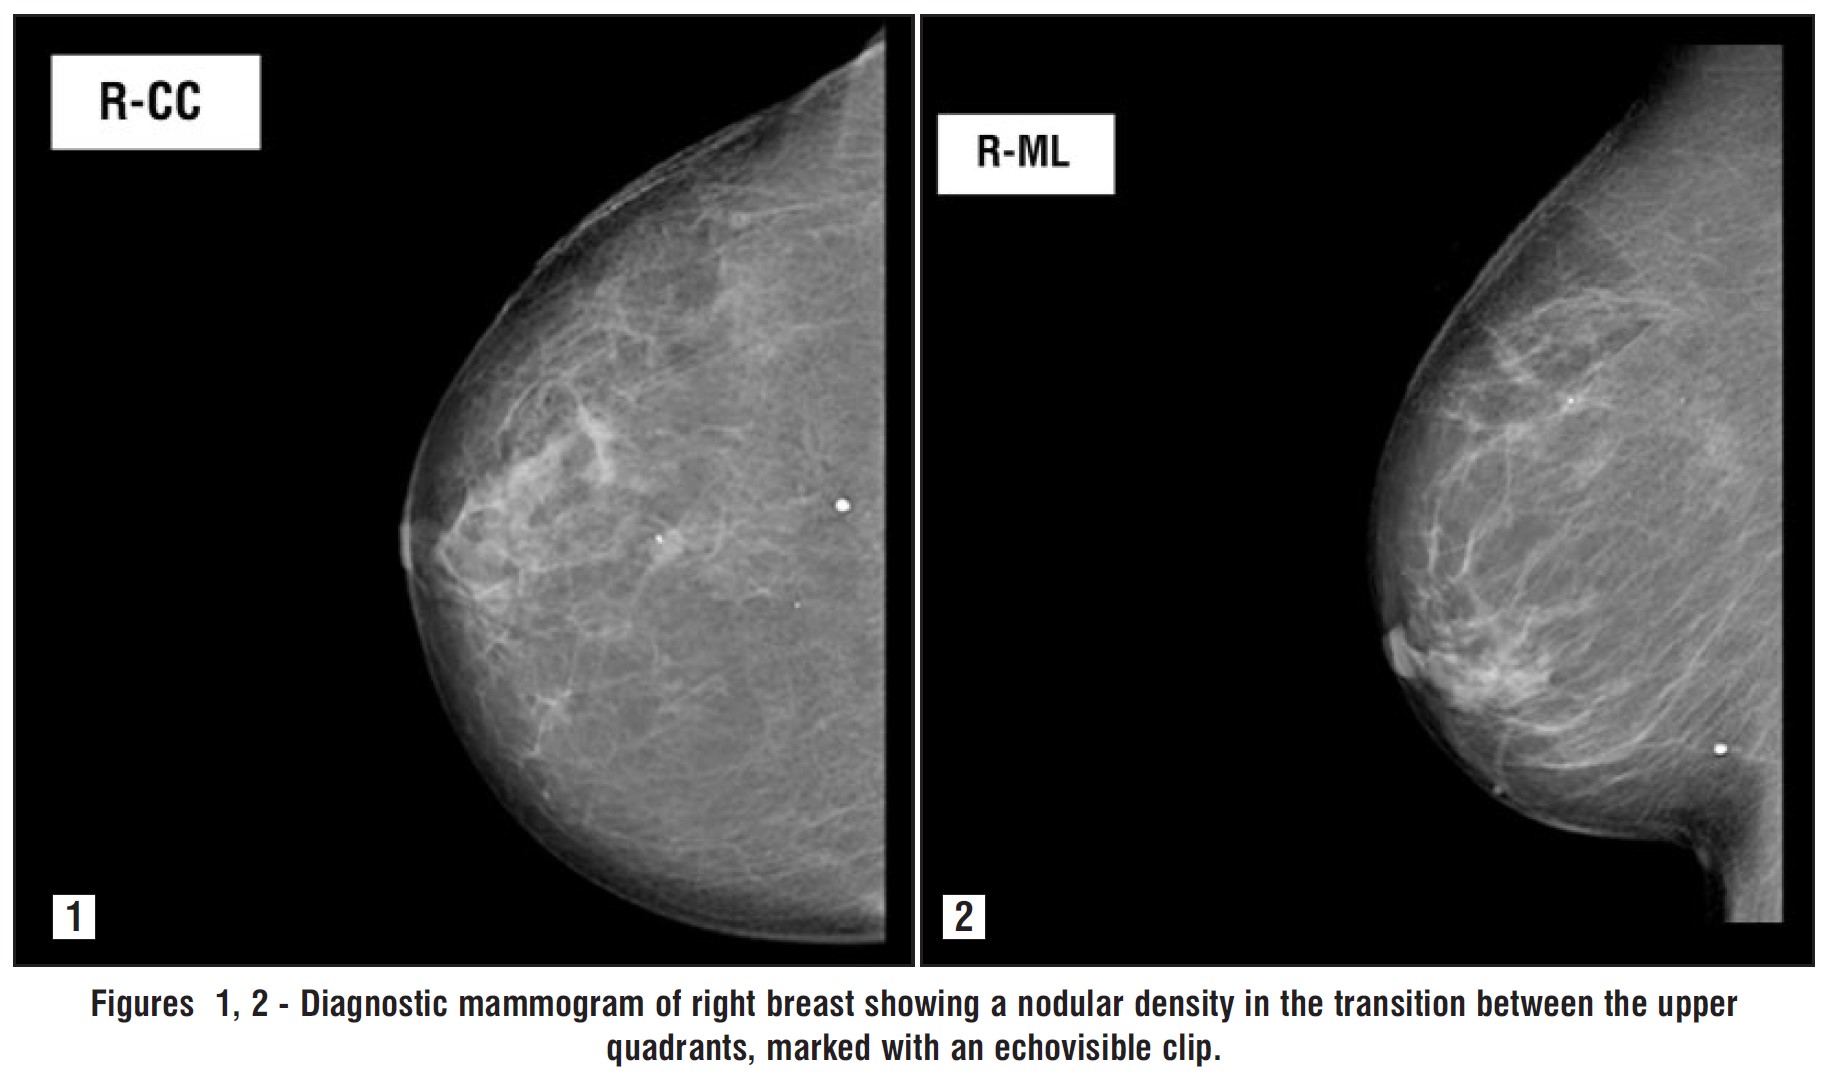

The patient did a screening mammogram (figs. 1 and 2), followed by a bilateral breast ultrasound, that showed a nodular density measuring 8 mm, projecting into the transition between the upper quadrants of the right breast. This finding was classified as BIRADS 4B. A percutaneous biopsy of the breast nodule was performed, and the pathologic examination was consistent with a metastasis of an ileal neuroendocrine tumor.

Figures 1, 2 - Diagnostic mammogram of right breast showing a nodular density in the transition between the upper quadrants, marked with an echovisible clip.